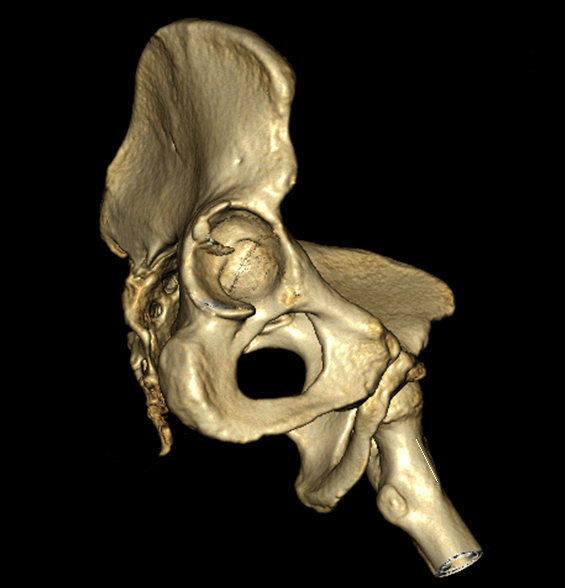

>> За праздники поступил еще один Pipkin IV. Женщина 30 лет, пострадала в

>> ДТП (пассажир). Сочетанная травма (ISS 25). Множественные переломы ребер с

>> двух сторон с пневмотораксом  и пневмомедиастинумом. Закрытый перелом

>> пилона справа. Задний переломо-вывих головки правой бедренной кости (Pipkin

>> IV). Ожирение III- IV  степени. Пацинентка в реанимации, состояние остается

>> тяжелым.

>> довольно сносную картину результата репозиции. Отломок головки оставался в

>> полости сустава во время вывиха, т.к. видимо сохранилось прикрепление со

>> связкой.  На КТ остается широкой суставная щель, что косвенно может

>> указывать на интерпозицию мягкими тканями, либо "встать на место" мешает

>> медиальный отломок головки.

>> Тактика остается прежней: после стабилизации состояния пациентки

>> выполнить задний доступ по Kocher-Langenbeck с флип-остеотомией большого

>> вертела и задним вывихом головки бедра. Остеосинтез головки винтами.

>> Ревизия полости сустава и далее по ситуации.